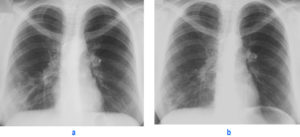

До начала лечения проводится диагностика. Обследования назначает пульмонолог. Большое значение имеет прослушивание лёгких, при пневмонии слышны специфические хрипы. В лаборатории проводится анализ крови, мокроты при откашливании, мочи. Больше всего информации врач получает после прохождения рентгена, УЗИ лёгких, эхокардиографии, томографии грудной клетки.

При обследовании нужно разграничить воспаление лёгкого с правой стороны и левостороннюю очаговую пневмонию. Диагностика помогает определить в какой части расположен очаг инфекции.

Верхнедолевое воспаление считается опасным — почти всё лёгкое поражено болезнью.

Расположенное рядом сердце может не выдержать длительной высокой температуры и патогенных микроорганизмов, поэтому лечение нужно начинать немедленно.

- рентгенографию легких (очаг болезни на снимке выглядит затемненным, а на поздней стадии – осветленным);